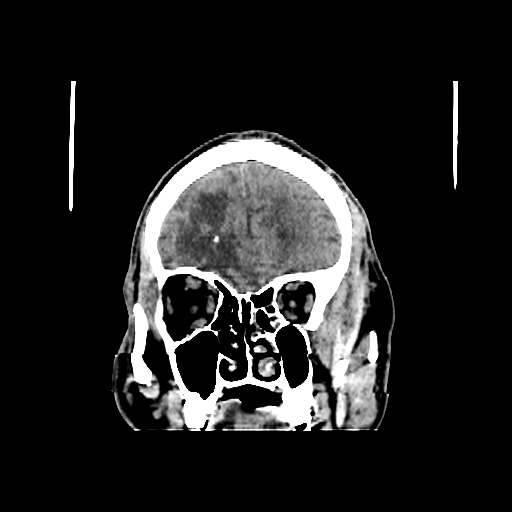

A 60 years old man with seizure since 12 years

Plan CT scan was done on 22 march 2016